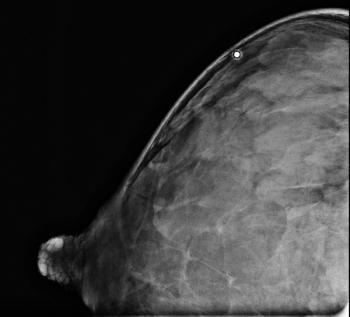

50-year-old patient presented for screening mammogram. Extremely dense breast tissue was noted.